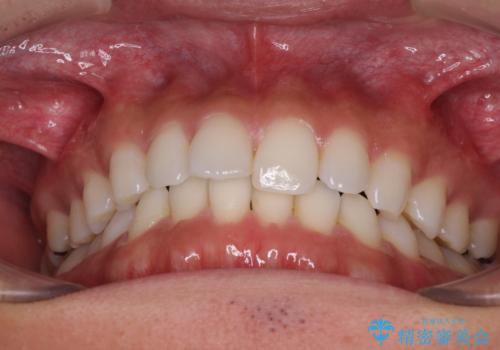

- 上下前歯のデコボコを気にして来院された患者様です。

以前矯正をした後戻りということで、歯列不正はそれほど大きくなかったため、インビザライン・ライトを用いて矯正治療を行うこととしました。